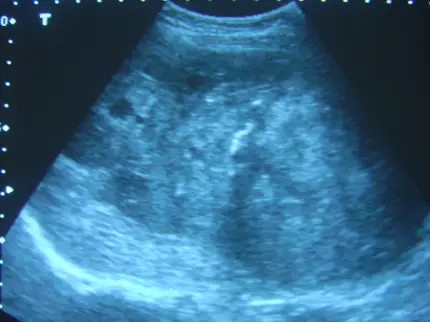

第一張圖(肝臟橫斷面超音波)

- 肝臟實質回聲稍增粗,肝邊緣平滑,無明顯邊界清晰、中央低回聲的圓形病灶,也無高回聲、後方明顯聲影的鈣化點。

- 結構呈大致均質的肝實質,未見典型的 hemangioma、高回聲斑點或惡性腫塊特徵。